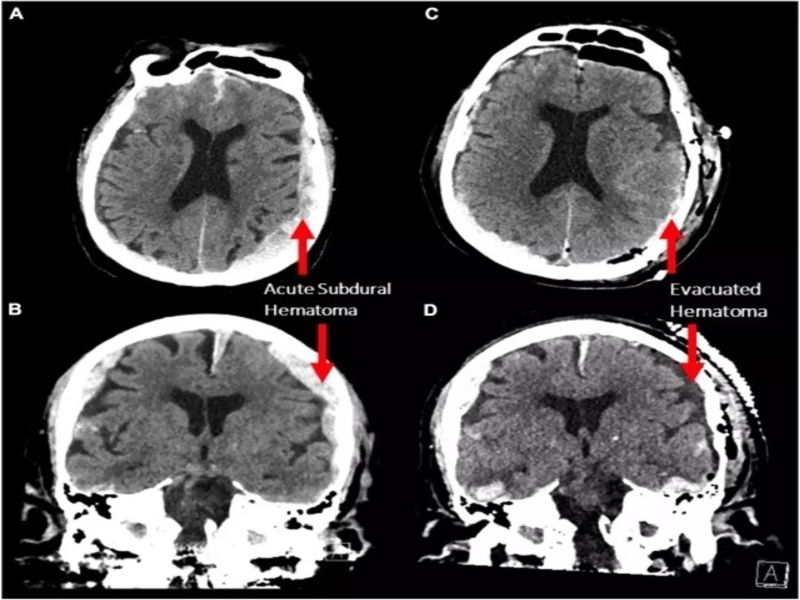

Фото: Frontiers in Ageing Neuroscience